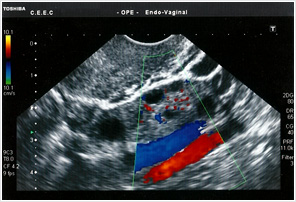

Ecografia ginecológica com Doppler

Permite avaliar a vascularização do útero e dos ovários.